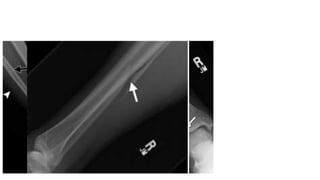

PER ( sấp- xoay ngoài)

• PER1: Gãy ngang mắt cá trong or

đứt dây chằng bên trong

• PER2: Đứt d.c syndesmosis trước

• PER3:  rách màng interosseous (

màng liên cốt) lan lên trên gây

gãy xương mác trên cao

• PER4: Vỡ mắt cá sau